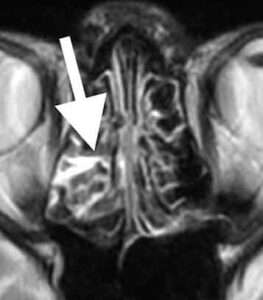

頭部MRA検査で脳の血管を撮影しました。

可逆性脳血管攣縮症候群

後大脳動脈という後頭部の血管が所々細くなっており(数珠状変化)、RCVSと診断しました。